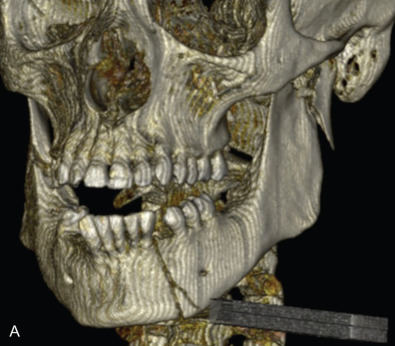

All of these systems allowed for convalescent function – life without MMF. RIF had the potential of dramatically shortening the course of treatment. However, its use was highly technique-sensitive with a steep learning curve. Thus, the incidence of complications increased dramatically due to operator error. Complications related to inadequate reduction – “the OIF” (open internal fixation … without the reduction) ( Figs. 1.16.1–1.16.3 ), inadequate fixation ( Figs. 1.16.4–1.16.7 ) and surgical misadventure ( Fig. 1.16.8 ) began to appear. Indeed, by the early 1990s operator error was the number one cause of mandibular fracture complications. Quite obviously, RIF is very unforgiving. When done poorly, one has a rigidly fixed mistake. The latest series of misadventures are related to the use of IMF screws. Bone-anchored arch bars will most likely be next. Not all believe that RIF and convalescent function is cost-effective with respect to the increased cost, potential for complications, and patient acceptance.